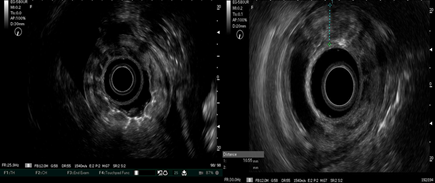

Ultrasonido endoscópico: Previa sedación con propofol y midazolam se introduce el ecoendoscopio radial hasta observar la mucosa de antro, se visualiza a nivel de toda la mucosa los pliegues gástricos muy engrosados, congestivos y erosionados en toda su superficie excepto en región pre-pilórica. A la visión ecográfica se observa engrosamiento fijo, difuso, circunferencial e irregular de toda la pared gástrica que oscila entre 8 y 12 mm de grosor, con mayor engrosamiento de la segunda, tercera y cuarta capa hipoecogénica, se observa además líquido libre perihepático a nivel del lóbulo izquierdo. Se procede a realizar biopsia por aspiración con aguja fina (BAAF) gástrica y cepillado de la mucosa para estudio cito-histopatológico. Conclusiones: linitis plástica gástrica difusa con ascitis ligera en relación con posible carcinosis peritoneal (Figura 1 y 2).